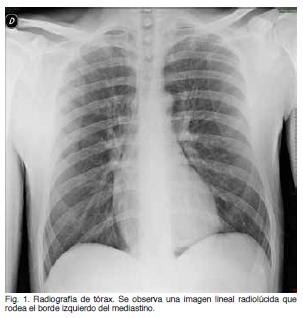

Se trata de un paciente de sexo masculino, de 18 años de edad, tabaquista leve. Consulta por dolor retroesternal de aparición en reposo, de 6 horas de evolución, opresivo, que irradia a cuello y aumenta con la inspiración profunda. Sin fenómenos acompañantes. Sin traumatismo de tórax, ni consumo de tóxicos inhalados previo al inicio de los síntomas. Del examen clínico se destaca: taquicardia regular de 100 cpm, con presión arterial de 120/70 mm Hg. Examen pleuropulmonar: normal. Electrocardiograma: taquicardia sinusal de 100 cpm. Radiografía de tórax (Figura 1) evidencia imagen lineal radiolúcida que rodea el borde izquierdo del mediastino. Se completa el estudio radiológico del tórax con una tomografía computada (Figura 2) en la que se evidencia gas (aire) disecando los grandes vasos mediastinales, alrededor el esófago y por delante del corazón.

Se presenta un caso de neumomediastino espontáneo. Las características epidemiológicas (edad de presentación, sexo), son concordantes con la literatura. No se encuentran factores desencadenantes en el caso relatado. En la literatura se identifican como desencadenantes todos aquellos factores que determinen un aumento de la presión intrapulmonar: acceso de tos, crisis asmática, vómito, maniobra de Valsalva, trabajo de parto, etc. Se ha asociado además al uso se cocaína, marihuana y éxtasis entre otros(3-5,8-10). La presentación clínica es heterogénea. Los síntomas más frecuentes son dolor torácico (presente en este paciente y en 63-89% de los casos según la serie) y disnea de intensidad variable (44-60%). Otros síntomas descritos son disfagia (3-67%), dolor generalizado de cuello (11-18%) y disfonía (5%), no presentes en el caso analizado(2,3,5-7,11,12). Los hallazgos clínicos más frecuentes son la presencia de enfisema subcutáneo en la escotadura supraesternal y el denominado signo de Hamman (40-80%) dado por la crepitación sincrónica con la sístole a nivel retroesternal, auscultándose mejor en decúbito lateral izquierdo(2,11,12). La presencia de pulso paradojal por aumento de la presión mediastínica es infrecuente(9). En el caso relatado el examen clínico es normal a excepción de la presencia de taquicardia sinusal. El diagnóstico de NE requiere un alto índice de sospecha, lo que determina que no sea considerado entre los planteos diagnósticos iniciales en un paciente joven con dolor torácico. En la radiografía de tórax se puede objetivar el signo del diafragma continuo (aire entre el pericardio y el diafragma), neumopericardio (aire anterior al pericardio en la radiografía lateral de tórax), signo de la V de Naclerio (aire entre la aorta descendente y el hemidiafragma izquierdo), resalte del contorno cardíaco y aire a nivel subcutáneo(2,11,13). La presencia de una columna estrecha e hiperclara en el mediastino y rodeando la silueta cardíaca es un hallazgo frecuente presente hasta en 90% de pacientes en algunas series (14). La tomografía computada de tórax permite confirmar el NE, valorar la extensión y descartar patologías asociadas(3,11). Los diagnósticos diferenciales a descartar son otras causas de dolor torácico que asocien enfisema subcutáneo como la perforación esofágica (síndrome de Boerhaave) y el neumotórax espontáneo(3,4). El tratamiento es habitualmente conservador en base a reposo, analgésicos y antitusígenos , como lo es el caso analizado. De haber compresión de las estructuras mediastínicas se puede realizar aspiración con aguja o por un catéter percutáneo colocado en el mediastino(15). En la mayoría de los casos el curso es benigno y autolimitado con reabsorción del aire ectópico en pocos días como sucedió en el caso descrito. En 9-16% la evolución puede ser fatal. Las recidivas son inhabituales(2,3,11).